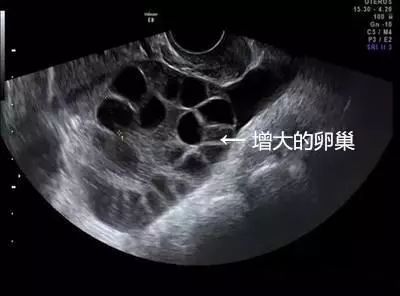

琳琳到这家妇幼保健院就诊时,B超提示腹腔内大量积液,胸腔少量积液,卵巢增大超过3倍以上,考虑是卵巢过度刺激综合症,被收治住院。

1.卵巢过度刺激综合征,尤其是瘦小、年轻的女孩子更容易得。卵巢增大导致卵巢壁毛细血管通透性增大,体液积聚于组织间隙,进而使引起腹腔积液、胸腔积液,甚至会导致血栓,危害生命。